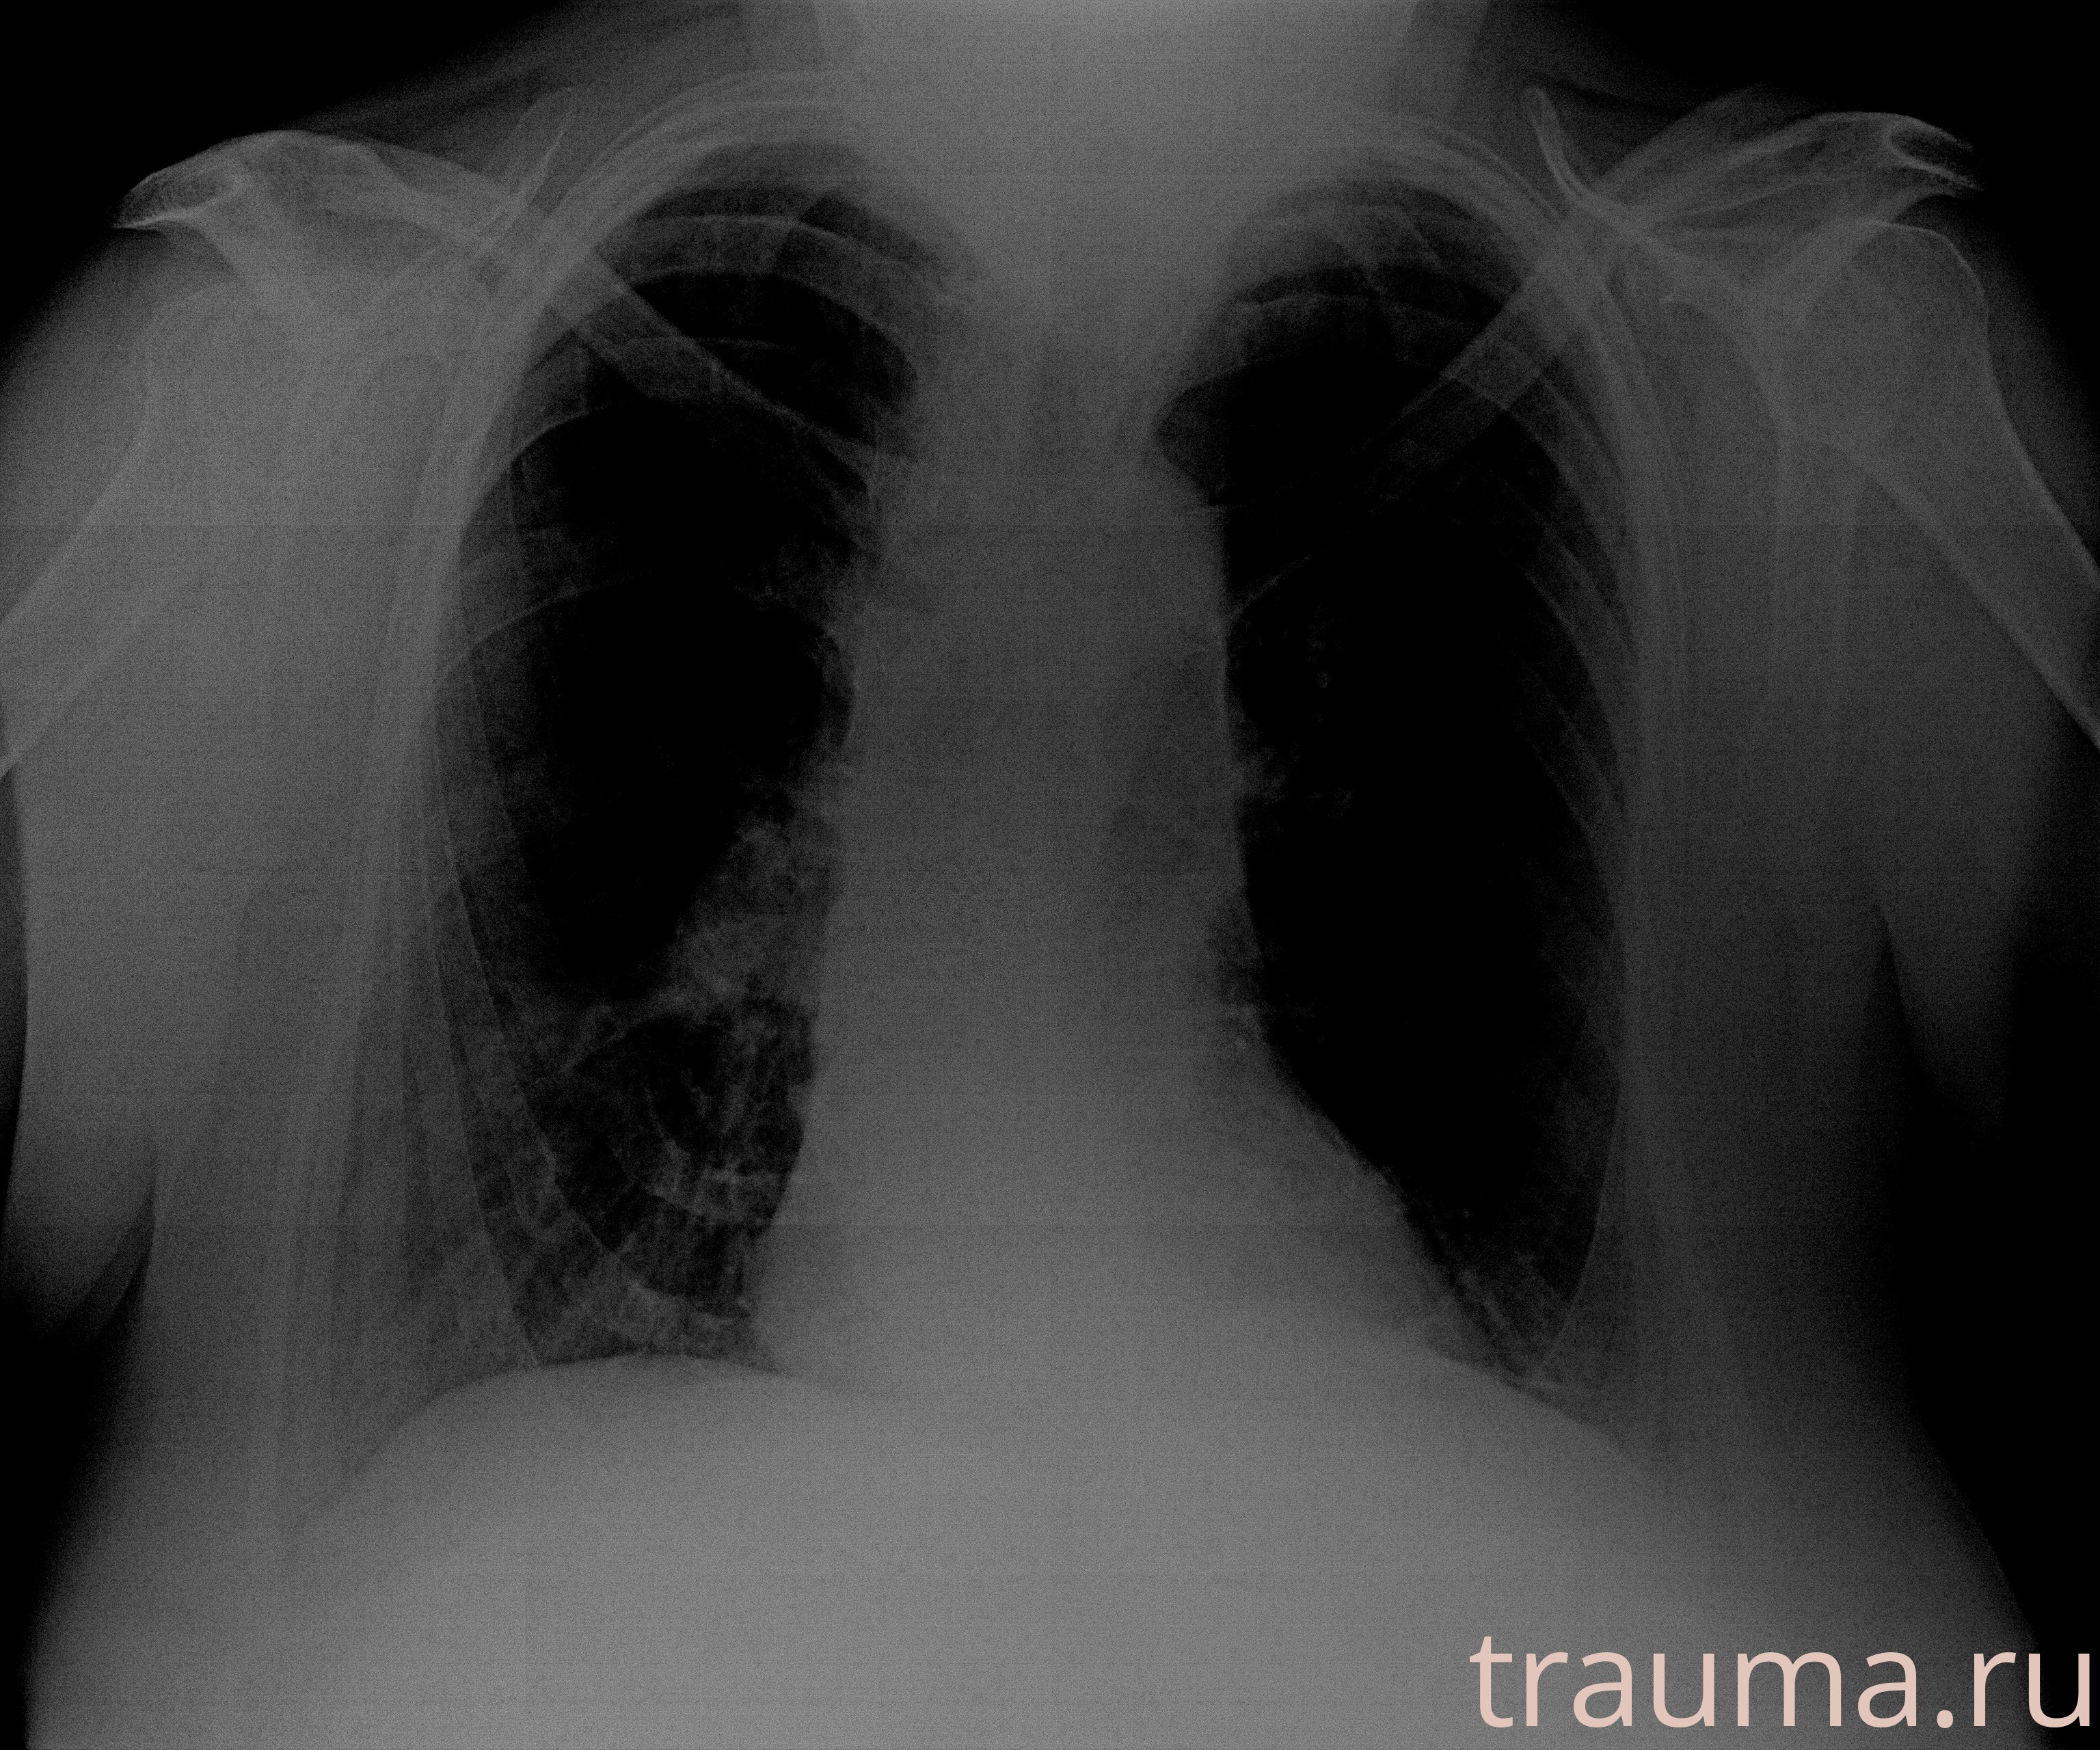

Рентген на дому: по вашему адресу приезжает врач-рентгенолог, травматолог-ортопед с мобильным рентгеновским аппаратом, проводит диагностику травмы или заболевания, делает необходимые рентгенограммы, дает рекомендации по дальнейшему лечению. Получить качественные снимки в домашних условиях возможно благодаря уникальной методике, разработанной МосРентген Центром для института  Склифосовского